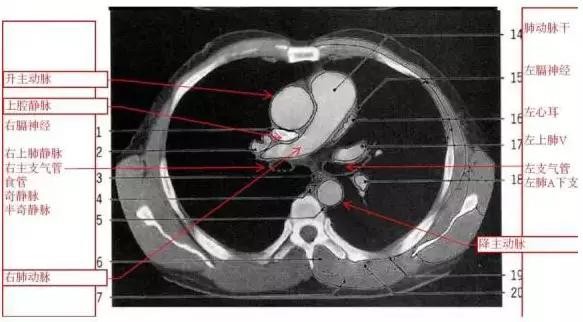

详尽的胸部CT影像示意图

胸部的CT是通过X线计算机体层摄影(CT)对胸部进行检查的一种方法。正常胸部CT层面较多,每一层面结构所表现的图像不同。下面是胸部CT图文示意图,可帮助临床医生详细了解CT结构。我们一起来看一下吧。

来源:影像论坛